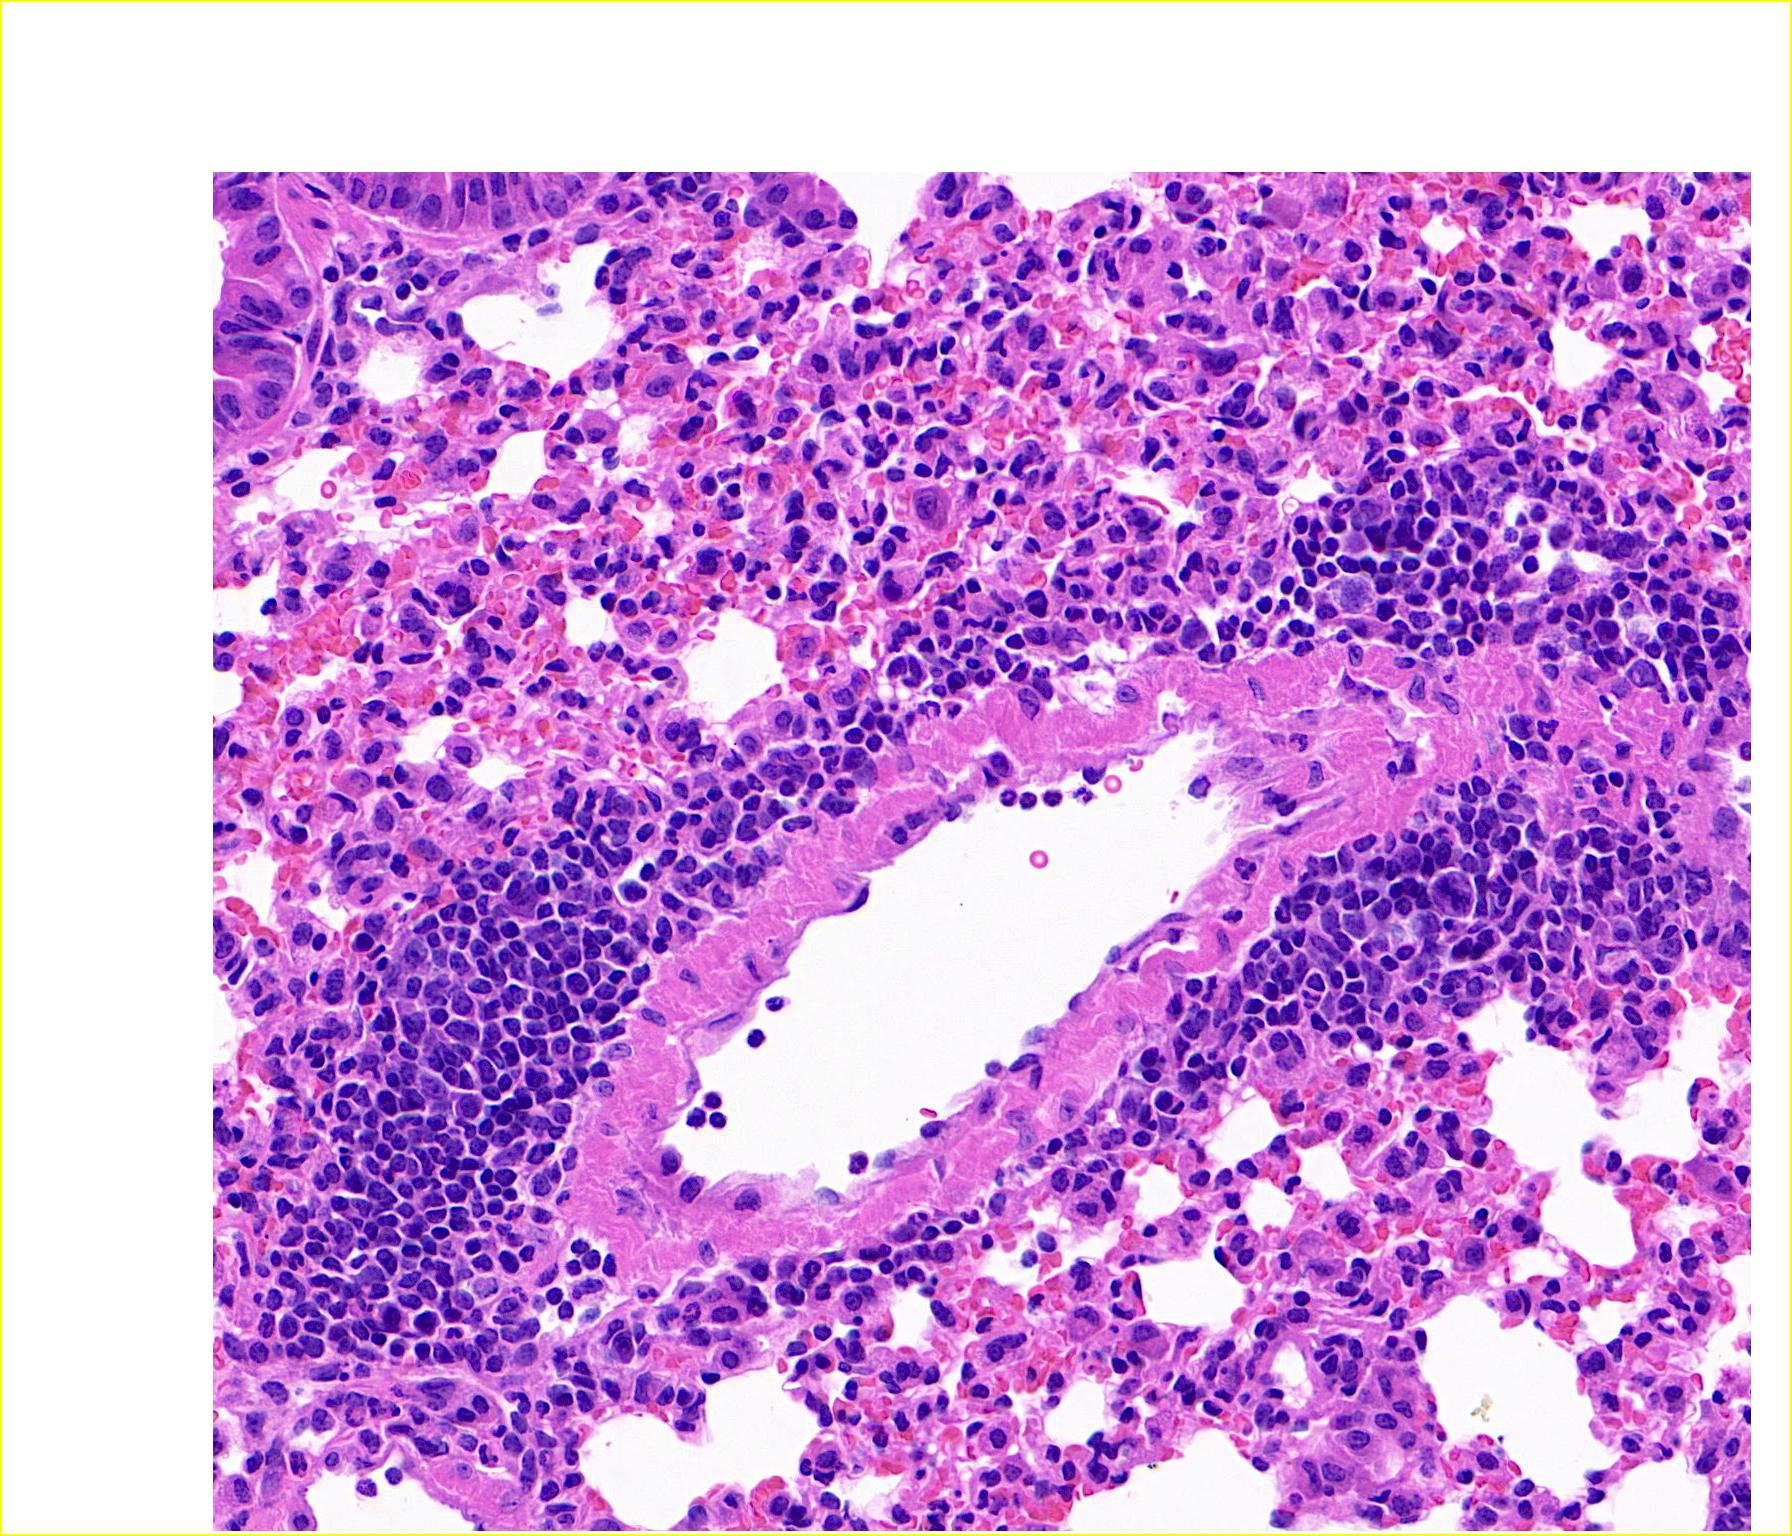

29 HE切片细胞类型

HE切片的细胞类型鉴定

以HE切片为例,直观理解就是确定每个细胞(核)属于哪种类型(比如中性粒细胞、上皮细胞、淋巴细胞等等)。